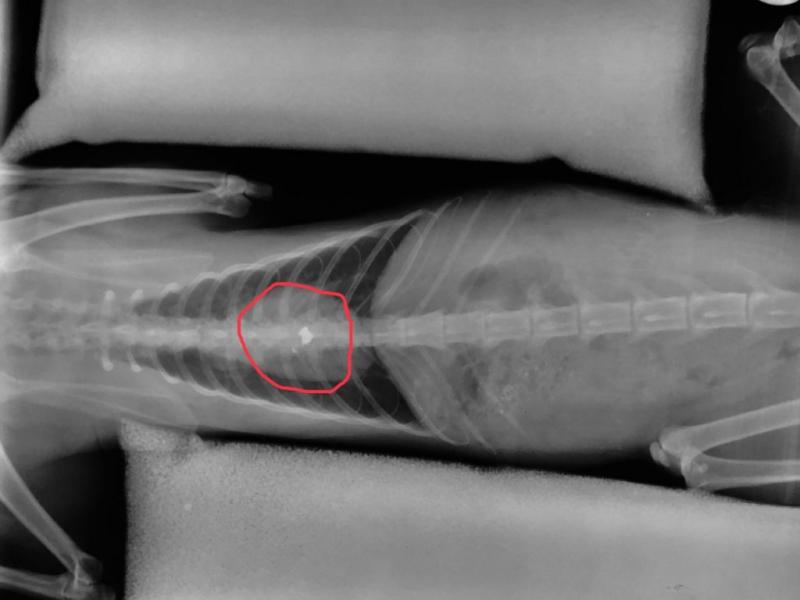

Σύμφωνα με τον αυτόπτη μάρτυρα που κατέθεσε ενώπιον του δικαστηρίου, ο εκπαιδευτικός βγήκε από το σπίτι του κρατώντας αεροβόλο όπλο, σημάδεψε τον γάτο που εκείνη την ώρα ζευγάρωνε και τον πυροβόλησε. Το άτυχο ζώο δέχθηκε τη σφαίρα στην σπονδυλική στήλη, όπως δείχνουν και οι ακτινογραφίες που κατατέθηκαν στο Δικαστήριο. Ο παράλυτος γάτος, φιλοξενήθηκε προσωρινά, στο σπίτι του ανθρώπου που βρέθηκε μπροστά στο συμβάν.

Ο φιλοζωικός σύλλογος απευθύνθηκε σε ιατρείο στην Λάρισα προκειμένου οι κτηνίατροι να αποφανθούν για την κατάσταση του γατούλη αλλά και το πως θα μπορούσε να αφαιρεθεί η σφαίρα που έχει σφηνωθεί στην ραχοκοκαλιά του και μάλιστα είχε βρεθεί άκρη αλλά δυστυχώς το άτυχο ζώο δεν άντεξε. “Τέτοιες συμπεριφορές προσβάλλουν την περιοχή μας, ειδικά όταν προέρχονται από ανθρώπους της εκπαίδευσης” τονίζει ο φιλοζωικός σύλλογος Λαμίας, που βρέθηκε στα δικαστήρια προκειμένου να “υπερασπιστεί” το γατάκι.